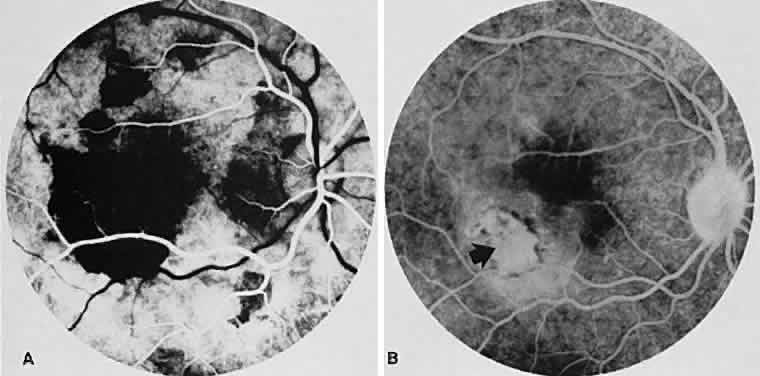

SERPIGINOUS CHOROIDOPATHY

Serpiginous choroidopathy, also known as serpiginous choroiditis, geographic, or helicoid choroidopathy, is an idiopathic, chronic, recurring peripapillary inflammation of the choroid and retinal pigment epithelium that spreads centrifugally. Frequently, only the macular region is affected, resulting in visual loss (Figs. 14 and 15). Although serpiginous choroidopathy can affect young persons, most patients are middle-aged or older. Active pigment epithelial lesions have a creamy geographic appearance and are at the level of the retinal pigment epithelium and choriocapillaris. Old lesions frequently show various amounts of retinal pigment epithelium/choriocapillaris loss with subretinal scarring and pigmentation surrounded by islands of normal choroid (Fig. 16A). There can be retinal vasculitis, iridocyclitis, disc swelling, periphlebitis, and, occasionally, vitreous cells. Disc neovascularization also has been seen. The disease usually begins unilaterally, although years later recurring episodes are common in one or both eyes. Asymmetric involvement also is very common.

Fig. 14. Macular serpiginous choroiditis. A. Red-free photograph of the left posterior pole shows the presence of a geographic lesion with diffuse borders at the level of the retinal pigment epithelium. B. Fluorescein angiogram of the left macular region shows a large area of choroidal hypofluorescence involving the macula. Other smaller hypofluorescent lesions surround the large lesion. Note pinpoint areas of hyperfluorescence representing drusen. C. The late venous phase shows diffuse staining of the left macular lesion.

Fig. 15. Subretinal neovascularization in serpiginous choroiditis. A. The arteriolar phase of the angiogram of the right eye shows a geographic center of choroidal hypofluorescence in the macula. There are additional areas of hypofluorescence superior to the right macular region. B. The venous phase of the angiogram shows a subretinal neovascular membrane just inferior and temporal to the macular zone (arrow). The hypofluorescence has decreased markedly in size compared with (A). The marked hypofluorescence masked the subretinal neovascular membrane initially.

Fluorescein angiography of the acute lesions shows early hypofluorescence due to blockage of the underlying choroidal fluorescence with eventual hyperfluorescent staining of the lesions' margins (see Fig. 14B and C). Later, there is patchy hyperfluorescence of the lesion due to leakage from the lesions' margins and from islands of normal choroid and choriocapillaris within the lesion. Sometimes the lesion becomes indistinguishable from the surrounding background fluorescence of the normal retina.46–48 The old lesions are hypofluorescent and are bordered by hyperfluorescence from the adjacent normal choriocapillaris. Hyperfluorescence of the old lesions occurs because of scar tissue that stains in the late phase of fluorescein angiography.

SRNV is a well-known complication of serpiginous choroidopathy. Occasionally, ophthalmoscopic signs such as subretinal blood and exudate can be seen. However, SRNV often appears like recurrent serpiginous lesions and can be diagnosed in patients only by fluorescein angiography, with persistent late enlarging hyperfluorescence of the lesions (see Fig. 15).49 The differential diagnosis includes AMPPPE, age-related macular degeneration, presumed ocular histoplasmosis, and choroidal ischemia.

In the acute stage, ICG angiography shows diffuse, homogeneous, marked, and persistent hypofluorescence during all phases of the angiogram in areas of active inflammation. Active choroidal involvement beyond the boundaries observed by ophthalmoscopy as well as those delineated by FA is noted. In the subacute phase of the disease, heterogeneous hypofluorescence with clear visualization of medium and large choroidal vessels is seen. In the healed stages, delayed or absent choroidal filling in the early transit phase with better visualization of deeper choroidal vessels because of loss of overlying RPE and inner choroid may be shown. If SRNV develops, hyperfluorescence of the lesion is noted.50,51